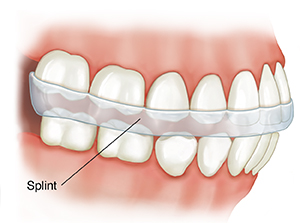

Teeth grinding (bruxism) or clenching strains the TMJ and related muscles. If you have these habits during the day, doing self-checks can help you stop. But it’s hard to control these habits when you’re asleep. That’s when using a splint may help:

How a splint works. A splint is an appliance that fits in the mouth. It may also be called an orthotic or night guard. There are different kinds of splints for different kinds of needs. A splint can keep the upper and lower teeth apart. This helps protect tooth surfaces from grinding. A splint can also be made to reduce strain on the area.

Wearing and caring for your splint. To make a splint, your dentist or orthodontist may take impressions of your teeth. Then a splint will be made to fit your mouth. A splint: